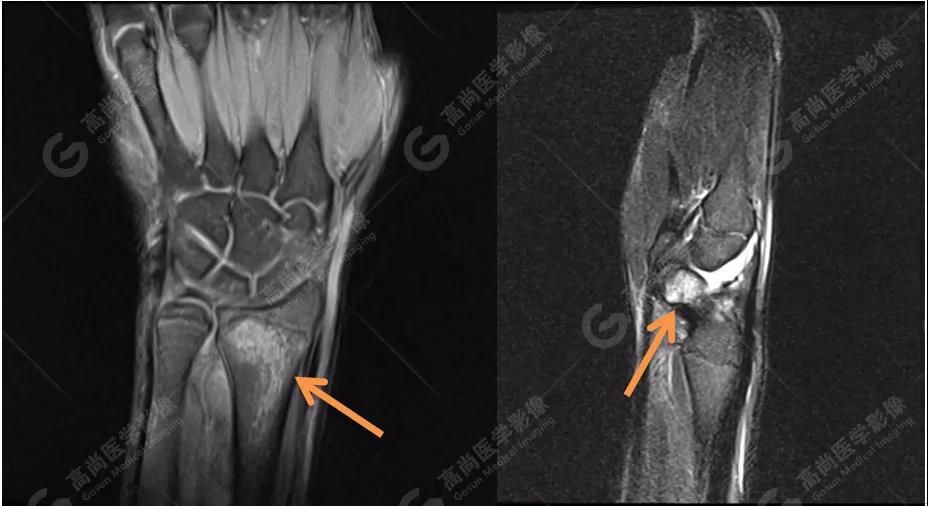

4、MRI圖像

MRI被認為是顯示骨髓水腫最好的方法。本著嚴謹、負責的態(tài)度,我們?yōu)椴』济赓M行MRI檢查,進一步確認診斷。

MR質(zhì)子壓脂序列圖像進一步證實:左側(cè)橈骨遠端與右側(cè)舟狀骨骨髓水腫!范圍也與雙能CT骨髓成像圖有很好的吻合度。